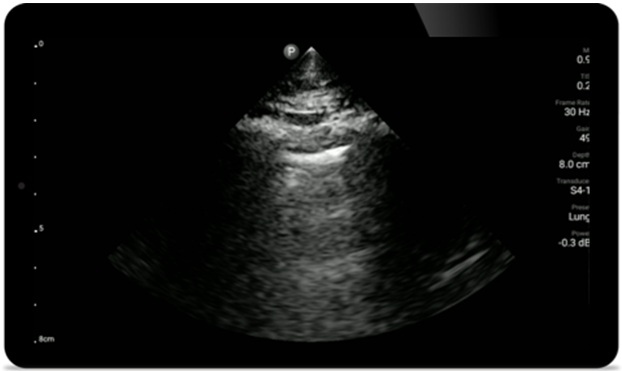

Gebruik Lumify voor luchtweg- en pulmonale beoordeling

De Lumify POCUS-oplossingen kunnen u helpen de endotracheale tube binnen de trachea te detecteren, ondersteuning te bieden bij urgente coniotomieprocedures, en diagnoses te stellen van pleurale effusie en interstitiële alveolaire ziekten.